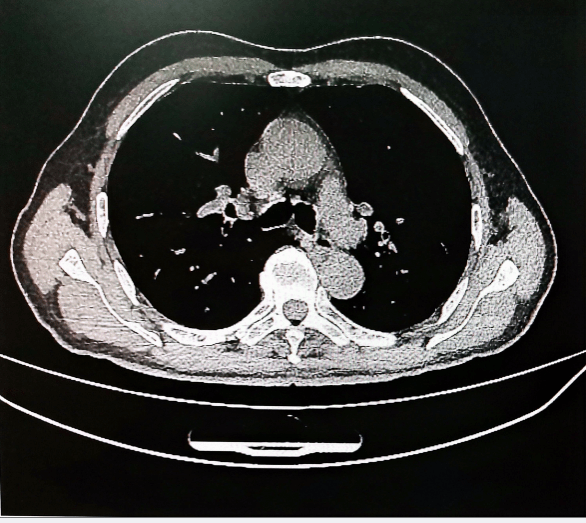

图2:术前上消化道钡透和胸部CT

该患者为局部晚期66岁老年男性食管癌患者(T4N3M0),前接受2 周期白蛋白紫杉醇 + 顺铂 + 免疫治疗。术前胸外科姜建涛主任、李少民教授、李建忠副主任及田运泽医生组织胸外科、中医科、普外科等多学科团队经充分评估,考虑到手术高难度源于患者 40 年前毕 Ⅱ 式吻合术导致胃体上移、肠道粘连,且残胃与空肠吻合,因此无法常规采用“管胃代食管术”或者“空肠带食管术式”,遂拟决定选择“胸骨后横结肠带食管吻合”方案。